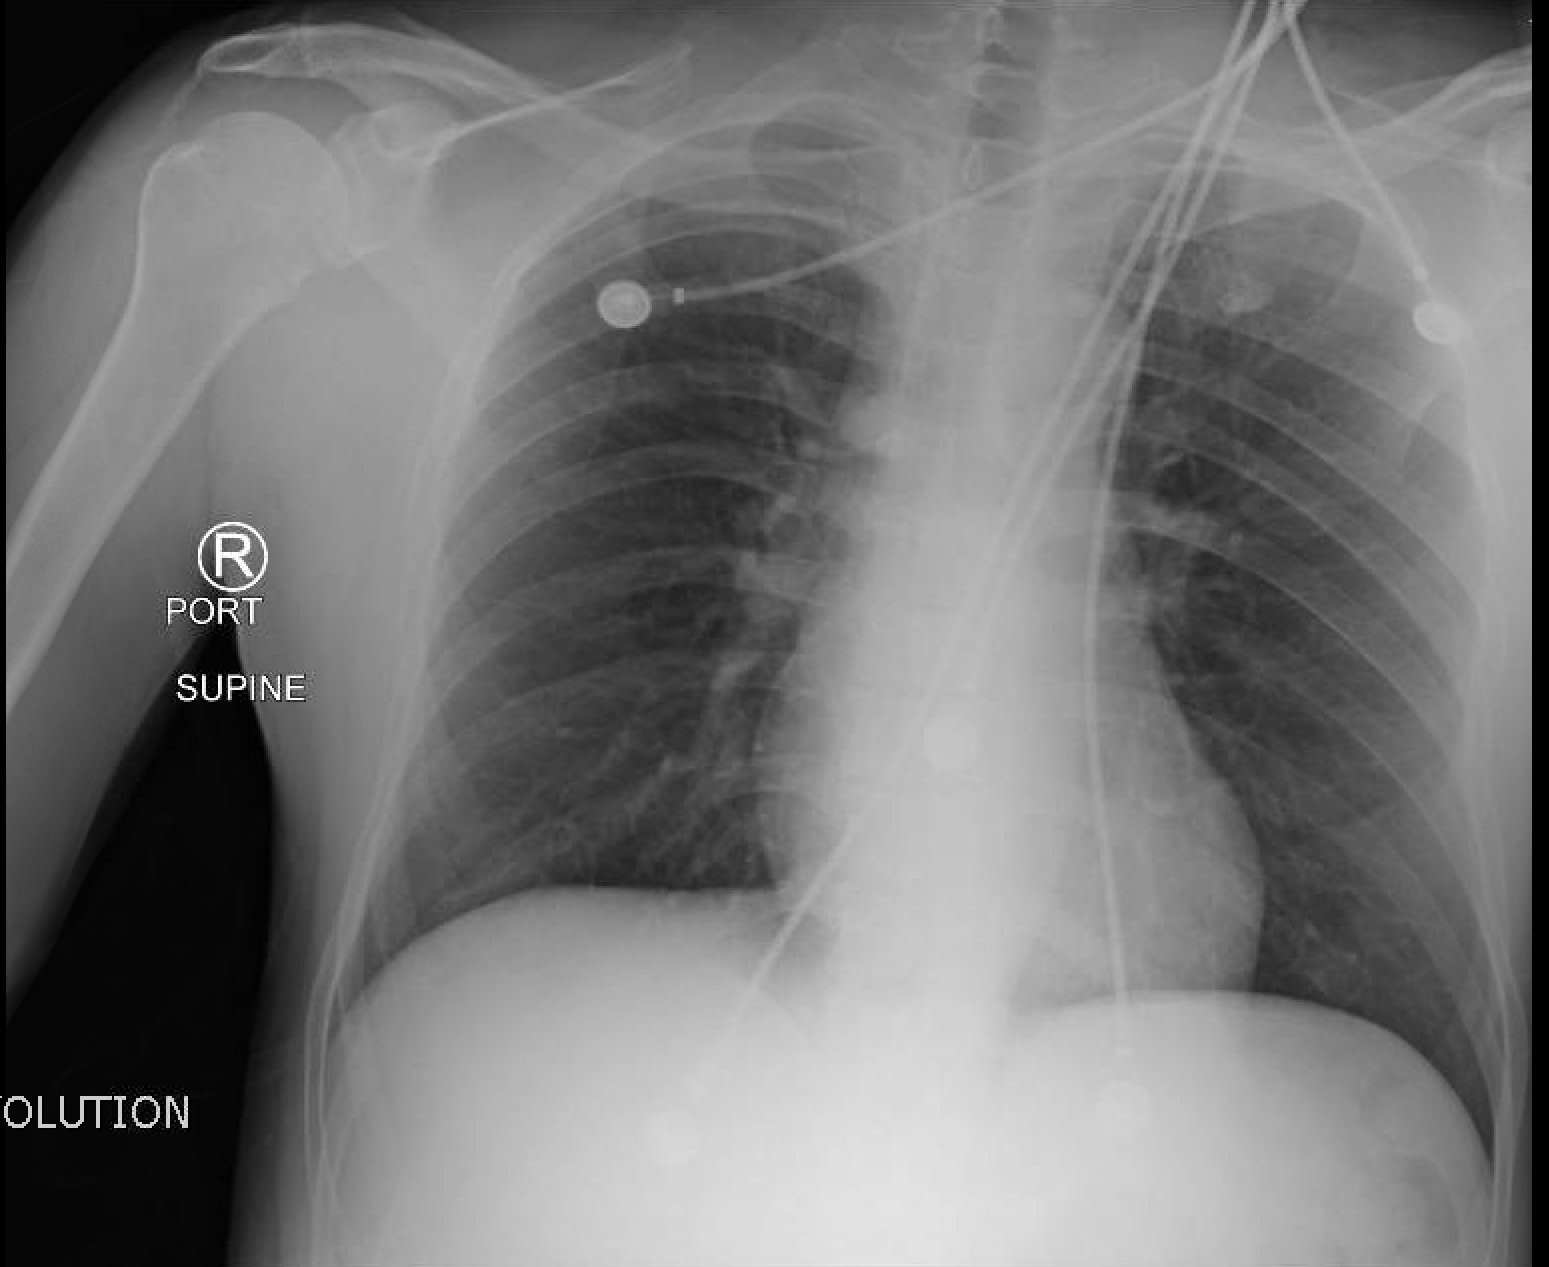

Normal CXR and Post-Intubation CXR

post intubation chest x-ray

Normal chest x-ray

radiology, normal, intubation, CXR, chest, respiratory, respiratory failure, AP, ETT, post-intubation

X-Ray